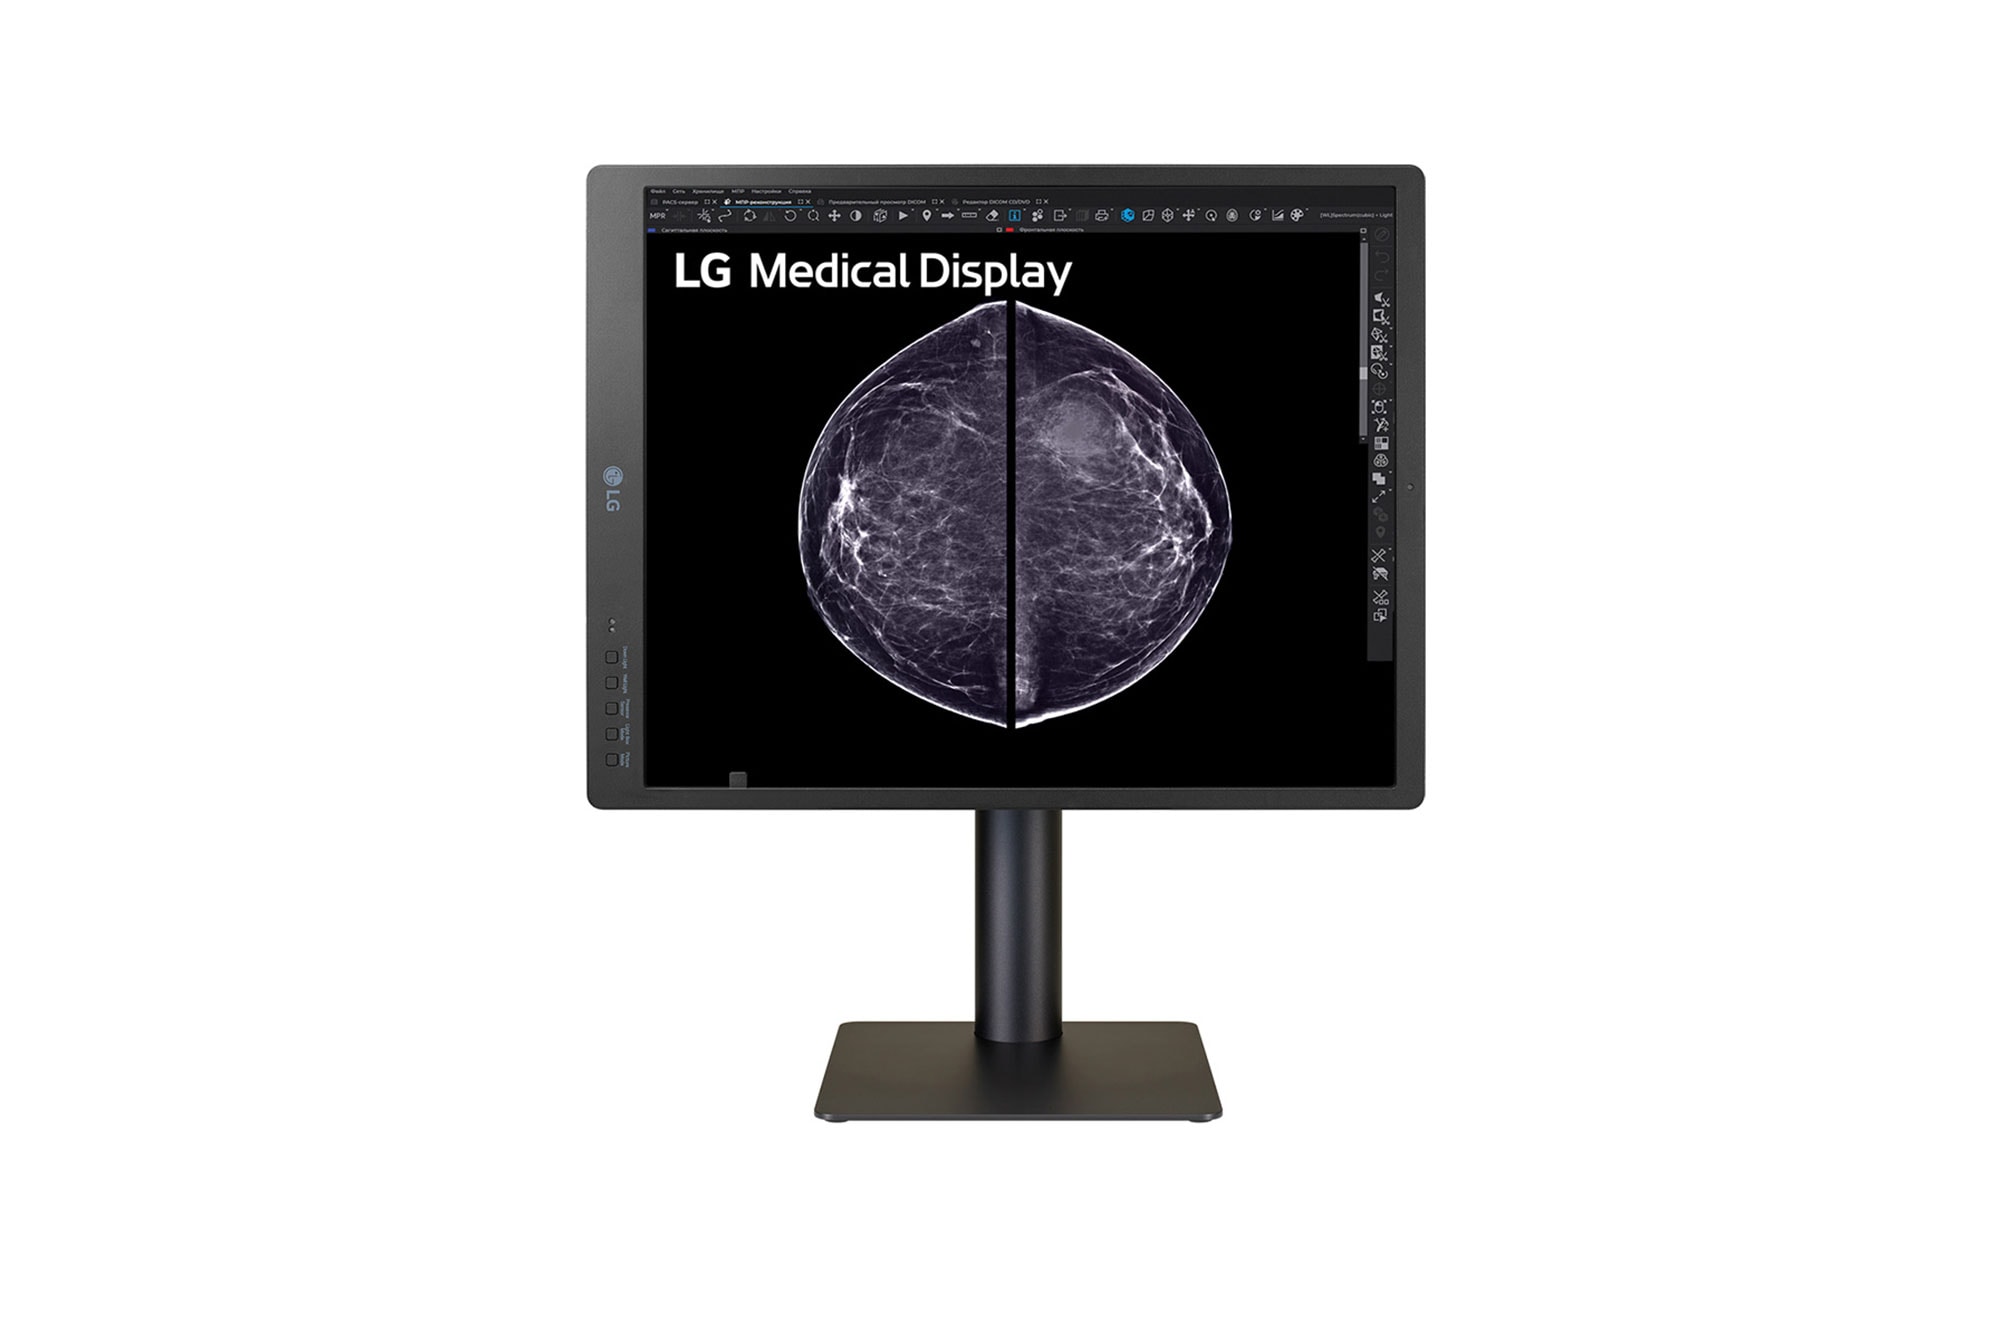

Display for breast imaging

21.3 (54.102 cm) 5MP (2048x2560) IPS Display

High resolution display for breast imaging

High Definition Imaging

Diagnostic Monitor 21HQ613D displays radiological images, including full field digital mammography and digital breast tomosynthesis, with a brightness of 1,100 cd/m² and a contrast ratio of 1,800:1. Moreover, this monitor showcases vivid colour, high definition mammography and breast tomosynthesis images including breast MRI, CT scans and ultrasound, ensuring versatile performance across various medical imaging modalities.

Diagnostic Monitor 21HQ613D displays radiological images, including full field digital mammography and digital breast tomosynthesis, with a brightness of 1,100 cd/m² and a contrast ratio of 1,800:1.